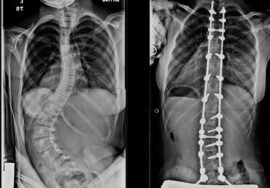

ثانيًا: علاج السبب الرئيسي

بعد استقرار الحالة، تم:

👉 إجراء جراحة لتصحيح اعوجاج العمود الفقري

حيث تم تثبيت الفقرات من مستوى T5 إلى L2.

ماذا كانت النتيجة؟

بعد الجراحة:

- تحسن شكل العمود الفقري

- توسعت الأوردة الرئوية بشكل طبيعي

- اختفى النزيف تمامًا

👉 وهذا يؤكد أن علاج السبب (الاعوجاج) هو المفتاح الأساسي للحل.